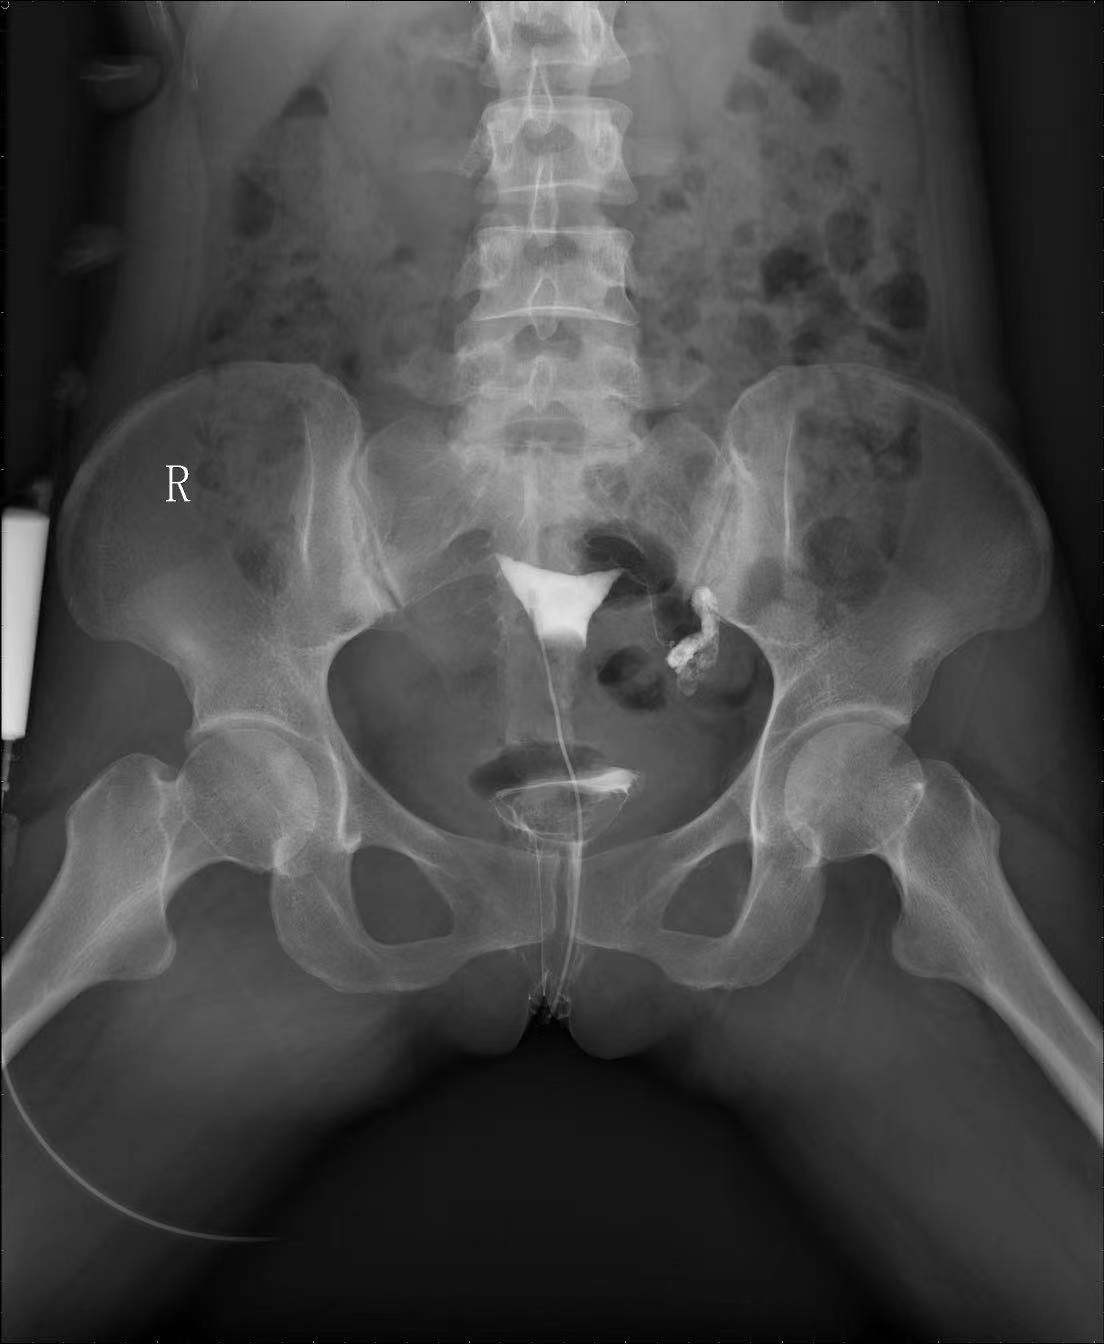

门诊子宫输卵管碘造影是通过向宫腔内注入碘伏醇造影剂,在X光下动态地观察造影剂在宫腔及输卵管的流动情况,实时立体的判断宫腔形态、输卵管管腔通畅性及其形态走行、以及造影剂盆腔弥散情况等。子宫输卵管造影已在妇产科临床中,特别是不孕不育患者的诊治中取得较好的效果,是一种安全、微创的检查新技术,能够快速、可重复地评价输卵管通畅性。

患者造影报告指出左侧输卵管远端(伞端)粘连、积水,左侧输卵管未显影。吴萍医生结合患者既往左侧输卵管妊娠,曾行腹腔镜下左侧输卵管切除术病史,以及患者阴道超声,性激素结果,给出患者治疗建议。

患者输卵管造影结果判读 :

该患者左侧输卵管远端扩张呈长形囊状,造影剂积聚于输卵管内,弥散平位片见盆腔内仍无造影剂。